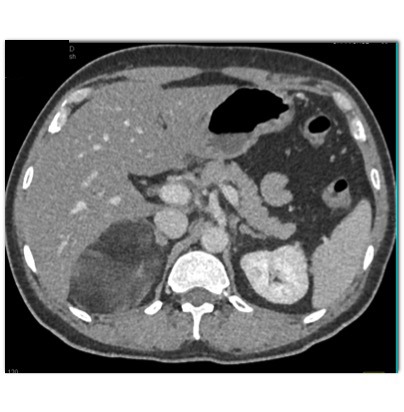

The best diagnosis in this case is?

Adrenal myelolipoma

Adrenal sarcoma

retroperitoneal liposarcoma

Adrenal carcinoma